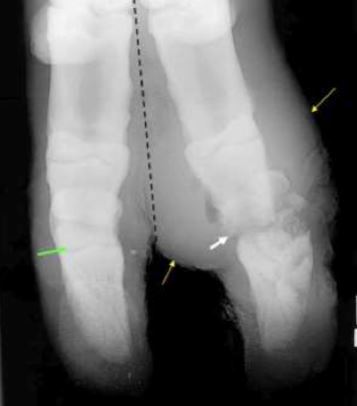

What might you see on rads of an

animal with septic DIJ?

A

Periosteal rxn

Asymmetric ST swelling

Bony lysis around joint

What’s your diagnosis if this malleable probe

is placed into the draining tract and

it falls right into the joint space?

Septic DIJ